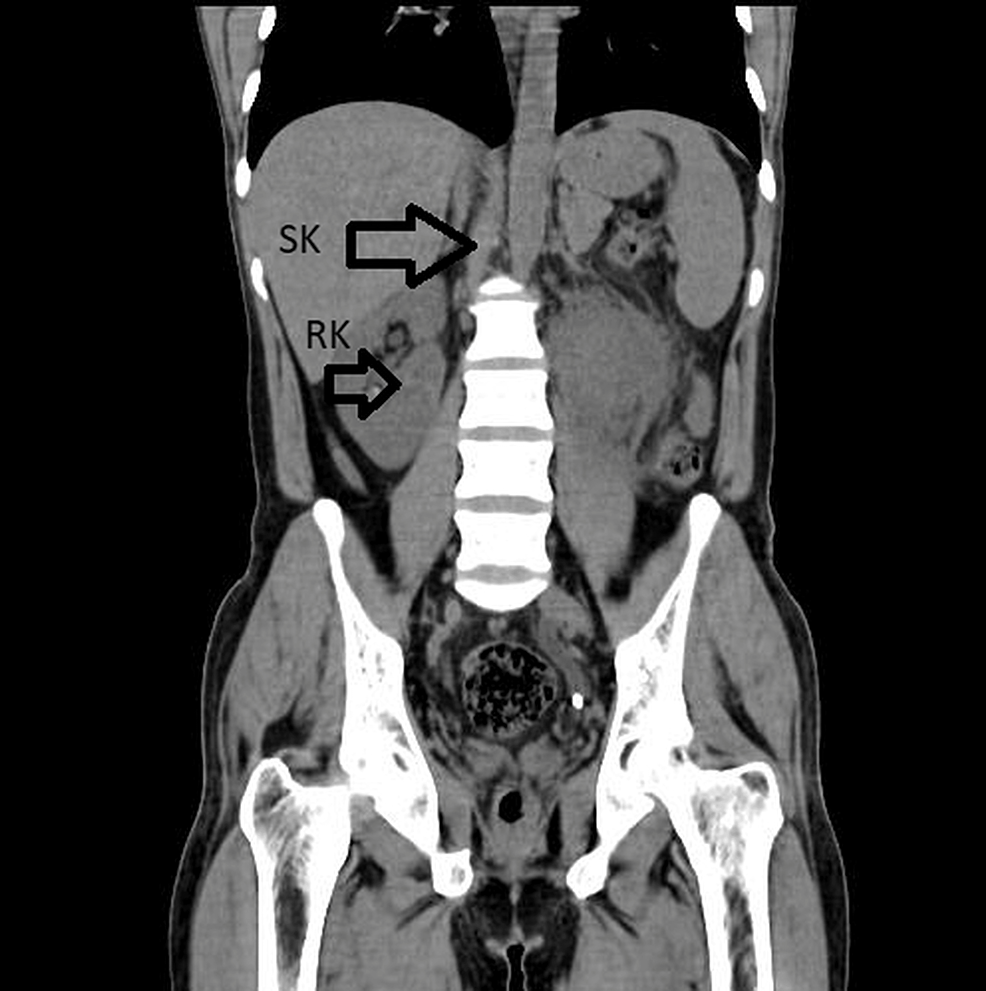

Horseshoe Kidneys with Cysts Kidney Case Studies CTisus CT Scanning

Horseshoe kidney CT wikidoc Horseshoe Shaped Kidney Complications An isolated finding of a horseshoe kidney is generally considered benign [3]. What complications are associated with horseshoe kidney? Seven in ten people with this. However, there is a higher incidence of upj. Interestingly, patients with horseshoe kidney seem to have an increased risk of a particular kind of kidney tumor called the wilms tumor. Up to 60% of patients. Horseshoe Shaped Kidney Complications.